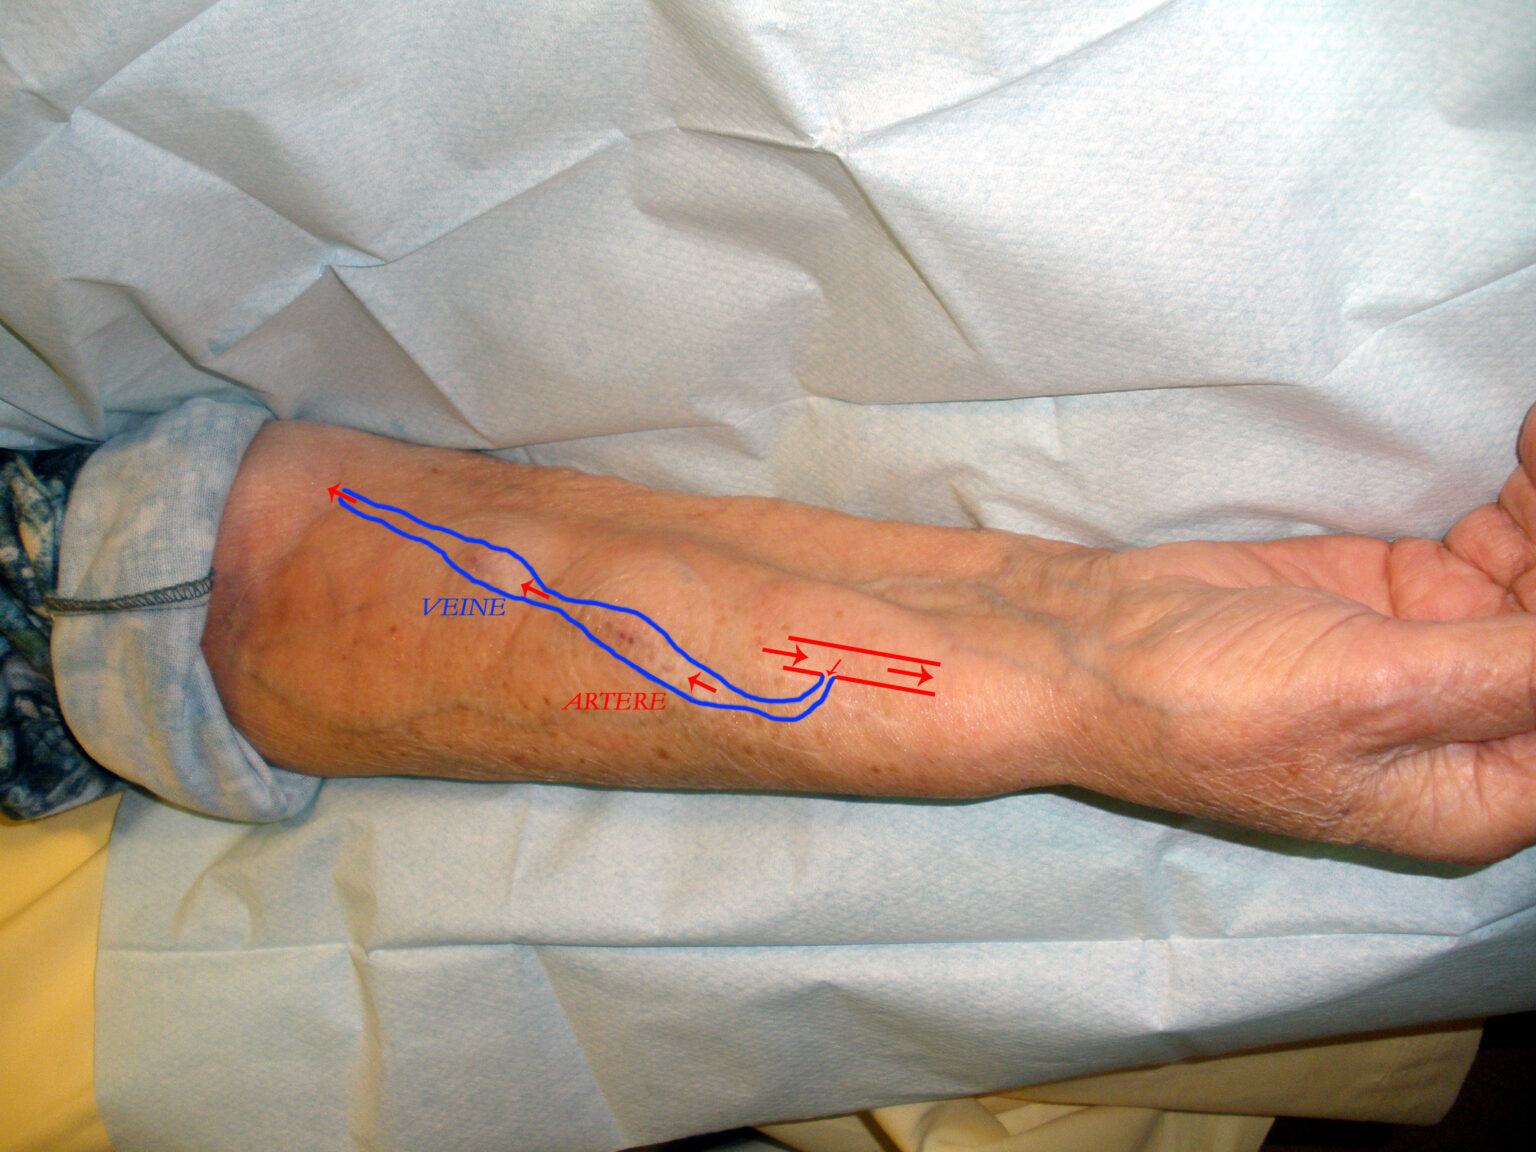

After the evaluation, you and your doctor will choose an access type. A fistula is created by surgically connecting an artery to a vein. Blood flow increases into the vein, and the vein expands and strengthens. A fistula may take several months to mature before it is ready for use.

Getting a graft is another option. A graft uses a soft, synthetic tube to connect an artery and a vein. The choice between a fistula and a graft depends on your vein health. Minimally invasive techniques are also available. These procedures create a fistula without open surgery. They use small catheters and wires inside the blood vessels. Available options may include: